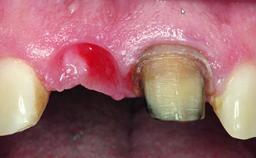

Replacement of a Failing Upper Left Central Incisor: Immediate Placement of an RC Bone Level Implant and Provisionalization

Soft Tissue Grafting Simultaneous

Soft Tissue Anatomy Intact Defective